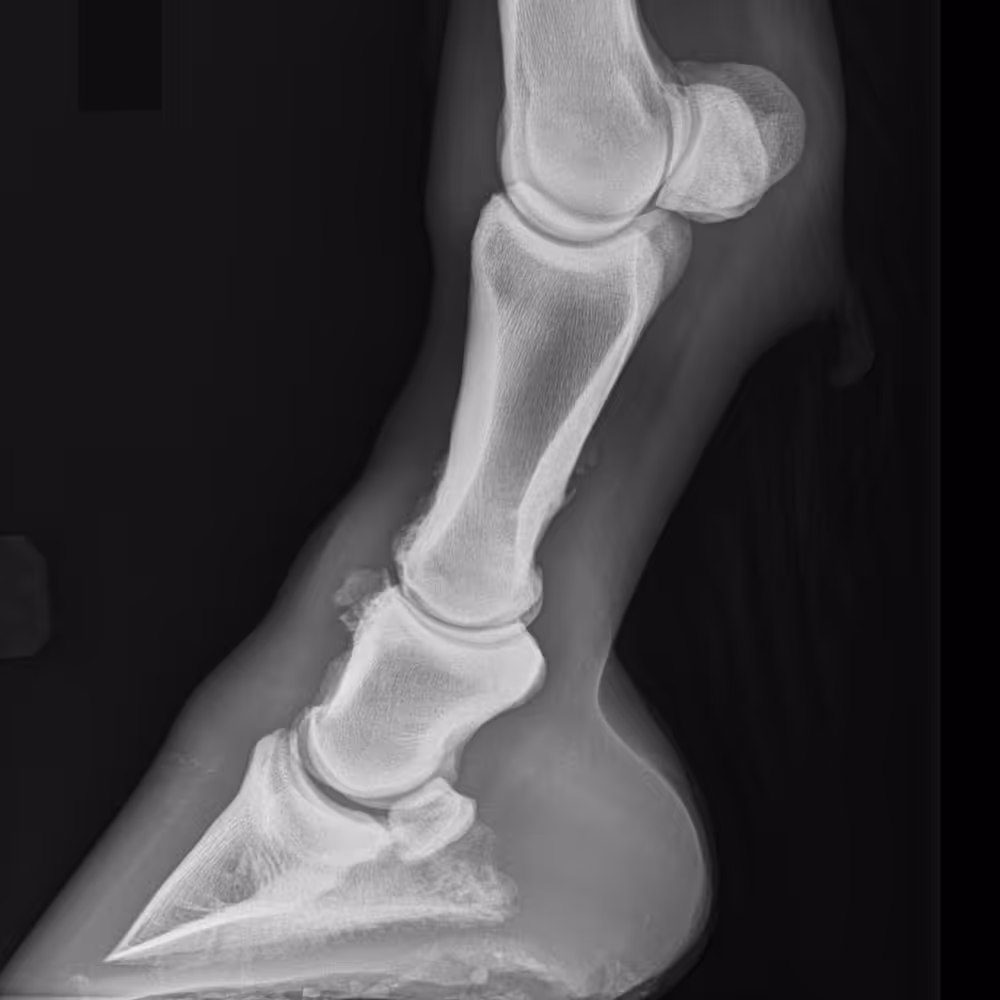

Severe OA of the proximal interphalangeal joint, with new bone proliferation dorsally and laterally, and joint space narrowing laterally.

X-ray image

Severe OA of the distal and proximal interphalangeal joints, with loss of definition of dorsal joint margins due to osteophyte formation and bone remodeling.